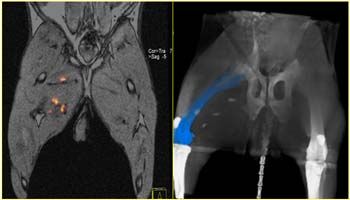

Diffusion-weighted MRI added to standard T2-weighted scans can help spot cervical cancer in its early stages. A preliminary study from the Institute of Cancer Research in London determined that DWI can spot tumors missed by T2 imaging and bolster management options for women who wish to preserve reproductive organs.